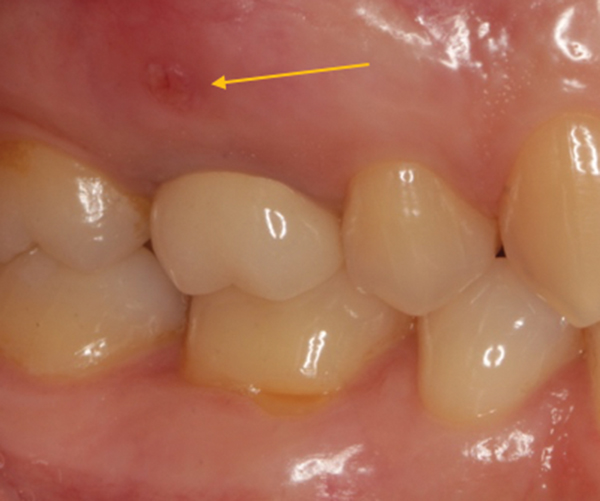

Fistula Gums

Fistula Gums What Is Dental Fistula A dental fistula is an abnormal channel that transports fluids, such as pus, from an area of inflammation to the exterior. A dental fistula is a small bump on your gums that forms when an infection inside your tooth needs a way to drain. Learn how to identify, treat, and prevent this oral health. Learn about the potential causes, recognizable. What Is Dental Fistula.